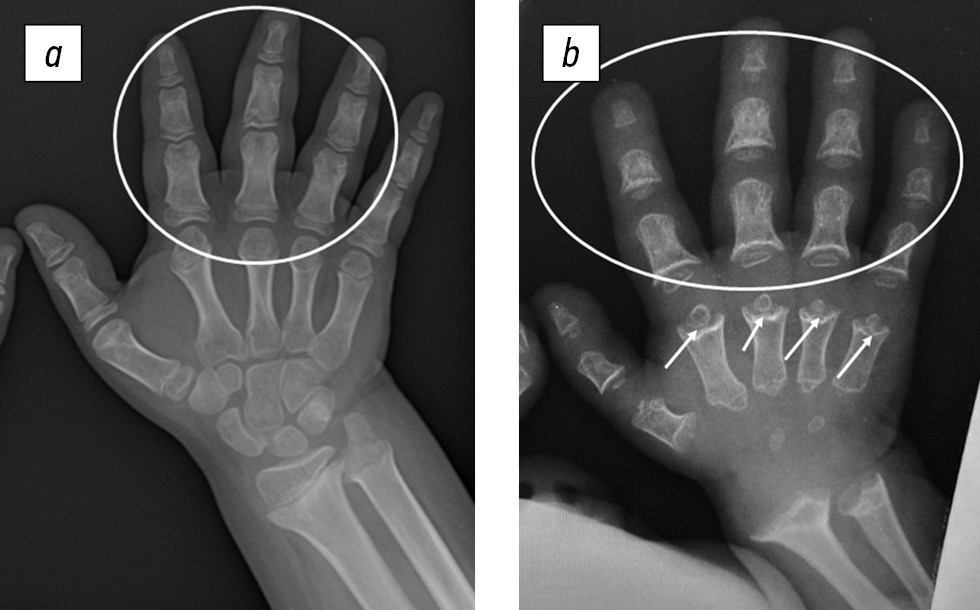

Рис. 5. Рентгенограмма кистей пациента с ахондроплазией (а) и псевдоахондроплазией (б): умеренная ульнарная девиация кисти и брахидактилия у обоих пациентов (отмечено белым контуром); укорочение пястных костей с чашеобразно расширенными метафизами и маленькими округлыми эпифизами по типу «шарика в гнезде» (ball-in-socket) у пациентов с псевдоахондроплазией (белые стрелки)

Диагностике ПСАХ в значительной степени способствовал анализ рентгенологических данных, в результате которого обнаруживали специфические изменения в виде задержки оссификации апофизов тел позвонков в детском возрасте, что определяло их характерную клювовидную форму на рентгенограммах позвоночника в боковой проекции, а также укорочение трубчатых костей с генерализованной задержкой оссификации эпифизов, проявляющейся уменьшением их размера, неправильной формой, неровными контурами. Кроме того, типичным было выраженное вовлечение метафизов в виде их расширения с неровностью (волнистостью и «изъеденностью») контуров. На рентгенограммах кистей наблюдали характерную картину в виде укорочения пястных костей с чашеобразно расширенными метафизами и маленькими округлыми эпифизами по типу «шарика в гнезде» (ball-in-socket) [18] (рис. 5).

Кисти | Короткие проксимальные и средние фаланги, расхождение II, III и IV пальцев («трезубец»), короткие пястные кости | Короткие фаланги; короткие пястные кости с конусовидными эпифизами и чашеобразными метафизами («шарик в гнезде») |